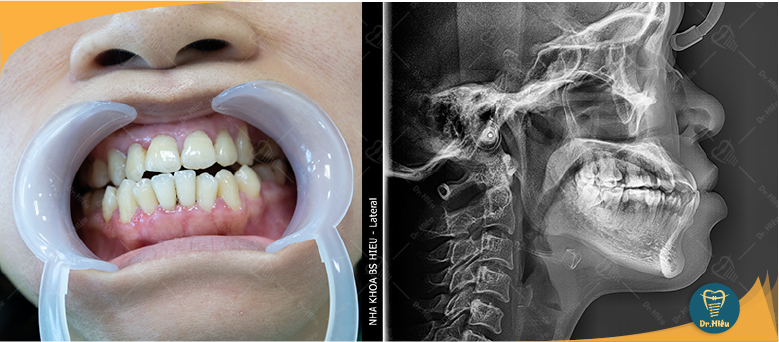

Răng hô, móm ảnh hưởng trực tiếp đến thẩm mỹ gương mặt và sự tự tin khi giao tiếp. Tại Nha Khoa Bác Sĩ Hiếu, niềng răng là lựa chọn phổ biến nhờ khả năng nắn chỉnh răng về đúng vị trí, giúp hàm răng đều đẹp và hài hòa.

Niềng răng là kỹ thuật nắn chỉnh giúp răng lệch lạc dịch chuyển dần về đúng vị trí trên cung hàm.

Khi răng đều đặn, vòm răng trên–dưới hài hòa hơn, cải thiện cả thẩm mỹ lẫn chức năng ăn nhai.

Nếu hô/móm do răng (không phải do xương hàm), bác sĩ thường chỉ định niềng răng. Dưới đây là các lựa chọn phổ biến: